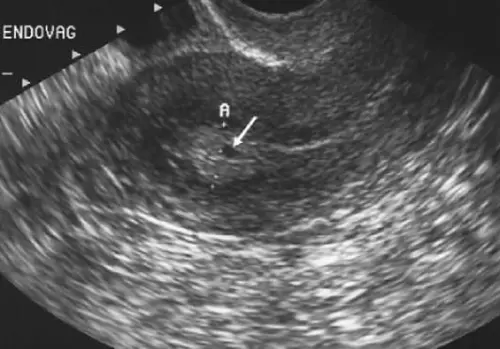

Цервікометрія — це безпечне УЗД шийки матки при вагітності, яке допомагає виміряти довжину шийки матки та оцінити її стан. Дослідження особливо важливе для запобігання ризиків передчасних пологів, зокрема у 2 триместрі, коли діагностична цінність процедури максимальна.

Цервікометрія в столиці включає діагностику стану шийки матки, що дозволяє точно визначити її довжину, ступінь розкриття та інші важливі параметри. Точність вимірювань при трансвагінальному УЗД шийки матки досягає 98%, що суттєво перевищує показники альтернативних методів діагностики.

Процедура проводиться в комфортній обстановці і займає 15-20 хвилин. При трансвагінальному УЗД шийки матки використовується спеціальний датчик із захисним покриттям. Процедура безболісна і не викликає дискомфорту.

Лікар проводить кілька вимірювань для отримання найбільш точних результатів. Під час дослідження пацієнтка може спостерігати за процесом на моніторі, а лікар коментує свої дії. У клініці Астрамедіка цервікометрія проводиться з дотриманням усіх сучасних стандартів, що забезпечує максимальну інформативність результатів.